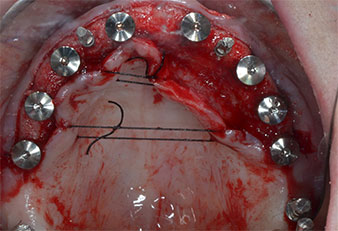

Three years later it was time for a maxillary denture of the same type. Based on CBCT planning sinus augmentation was avoided with the aid of short implants, and a surgical template was used to transfer the planned positions to the alveolar ridge (Figs. 1 and 2).

Fig. 1: Pre-operative view of the maxillary ridge, with implant positions marked with the aid of a surgical plastic template. Due to the low ridge super short posterior implants are planned.

Implant positions

Fig. 2: After mid-crestal incision and preparation of mucoperiosteal flaps the implant positions are transferred to the bone.

Due to the relatively hard bone (D2) in this area, the 10 mm long implant sites at positions 11 and 21 were finalized with a 4 mm diameter rotary drill, in combination with a W&H WS-75 L surgical contra-angle handpiece, the W&H Implantmed implant motor and the optional W&H Osstell ISQ module. In contrast, due to the soft bone the posterior sites were prepared to a final 3 mm diameter using the Piezomed I3P instrument. The implants were finally placed transgingivally to osseointegrate for three months (Figs. 6-10). The existing denture was retained on four provisional implants (Fig. 8).

10-mm tissue level implant

Fig. 6: A 10-mm tissue level implant is placed at position 21. The implant at position 11 and the three left posterior 4-mm implants are already in place.